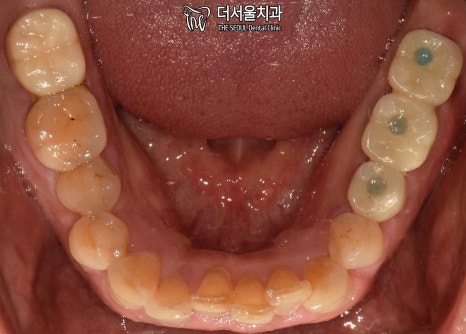

1. 구강 체크

서현역 치과를 찾아오셨던 환자분은

앞니와 왼쪽 끝 어금니에

이상 증세를 느껴 찾아오셨습니다.

겉으로 봤을 때는 큰 문제는 없는 것처럼 보입니다.

그럼 대체 무슨 문제가 있는 걸까요?

겉으로 보여지는 것이 아닌,

속을 들여봐야 알 수 잇겠네요.

엑스레이 촬영을 통해 체크해보겠습니다.